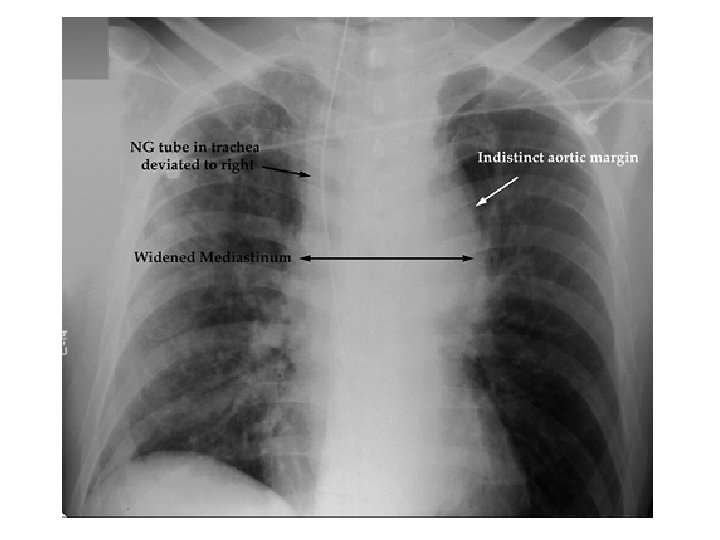

F. TRAVMATİK AORTİK YARALANMA • Otomobil kazaları ve yüksekten düşmelerden sonra yaygın ani ölüm nedenidir. • Kurtulan hastalarda Ligamentum arteriosumun yanından inkomplet laserasyon • İntakt adventisyal tabaka tarafında sürdürülen devamlılık veya mediastinal hematom ani ölümü önler. • Bir miktar kan mediastinuma kaçar. • Persistan ve rekürren hipotansiyon görülür. • Aortanın serbest rüptürü hasta hızlı şekilde opere edilmez ise fataldir. • Spesifik semptom ve bulgular genellikle yoktur. • Arteriografi ve radyolojik bulgular tanısaldır. • Aortogramların yaklaşık %3 ü aortic rüptür için pozitiftir.

• Major vasküler yaralanma olasılığını gösteren radyolojik bulgular: 1. 2. 3. 4. Geniş mediastinum Aort topuzunun obliterasyonu Trakeanın sağa deviasyonu Pulmoner arter ve aorta arasındaki obliterasyonu 5. Sol ana bronkusun depresyonu 6. Özefagusun sağa deviasyonu 7. Geniş paratrakeal şerit 8. Geniş paraspinal boşluk 9. Plevral yada apikal kep varlığı 10. Sol hemotoraks 11. Birinci yada ikinci kosta yada scapula kırığı boşluğun

Siyah oklar PLEVRAL APİKAL CAP’ı, Beyaz oklar PARATRAKEAL SERİT’i gösteriyor